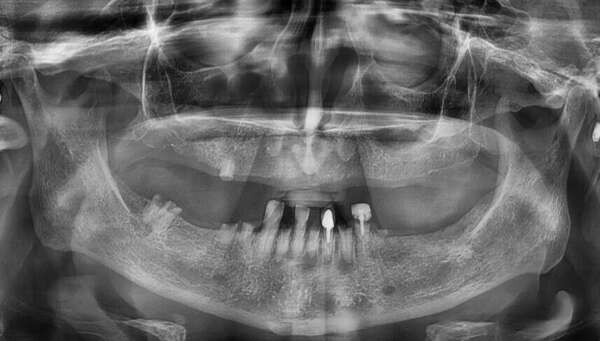

Cas de double mise en charge immédiate sur implants

Cas du Docteur Maxime Collangettes

Esthétique, mise en charge immédiate et implant de petit diamètre

pour remplacer une agénésie d incisive latérale maxillaire, chirurgie guidée